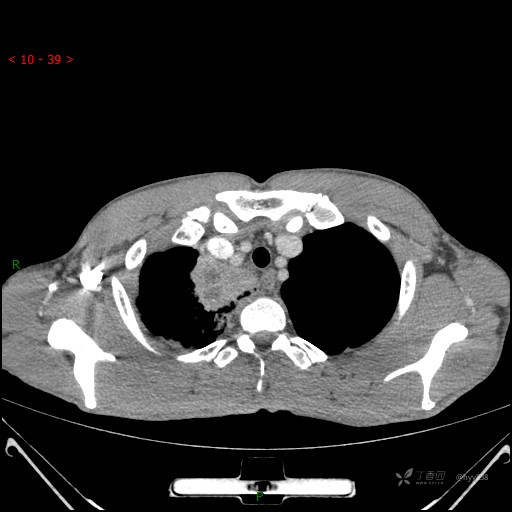

增强动脉期